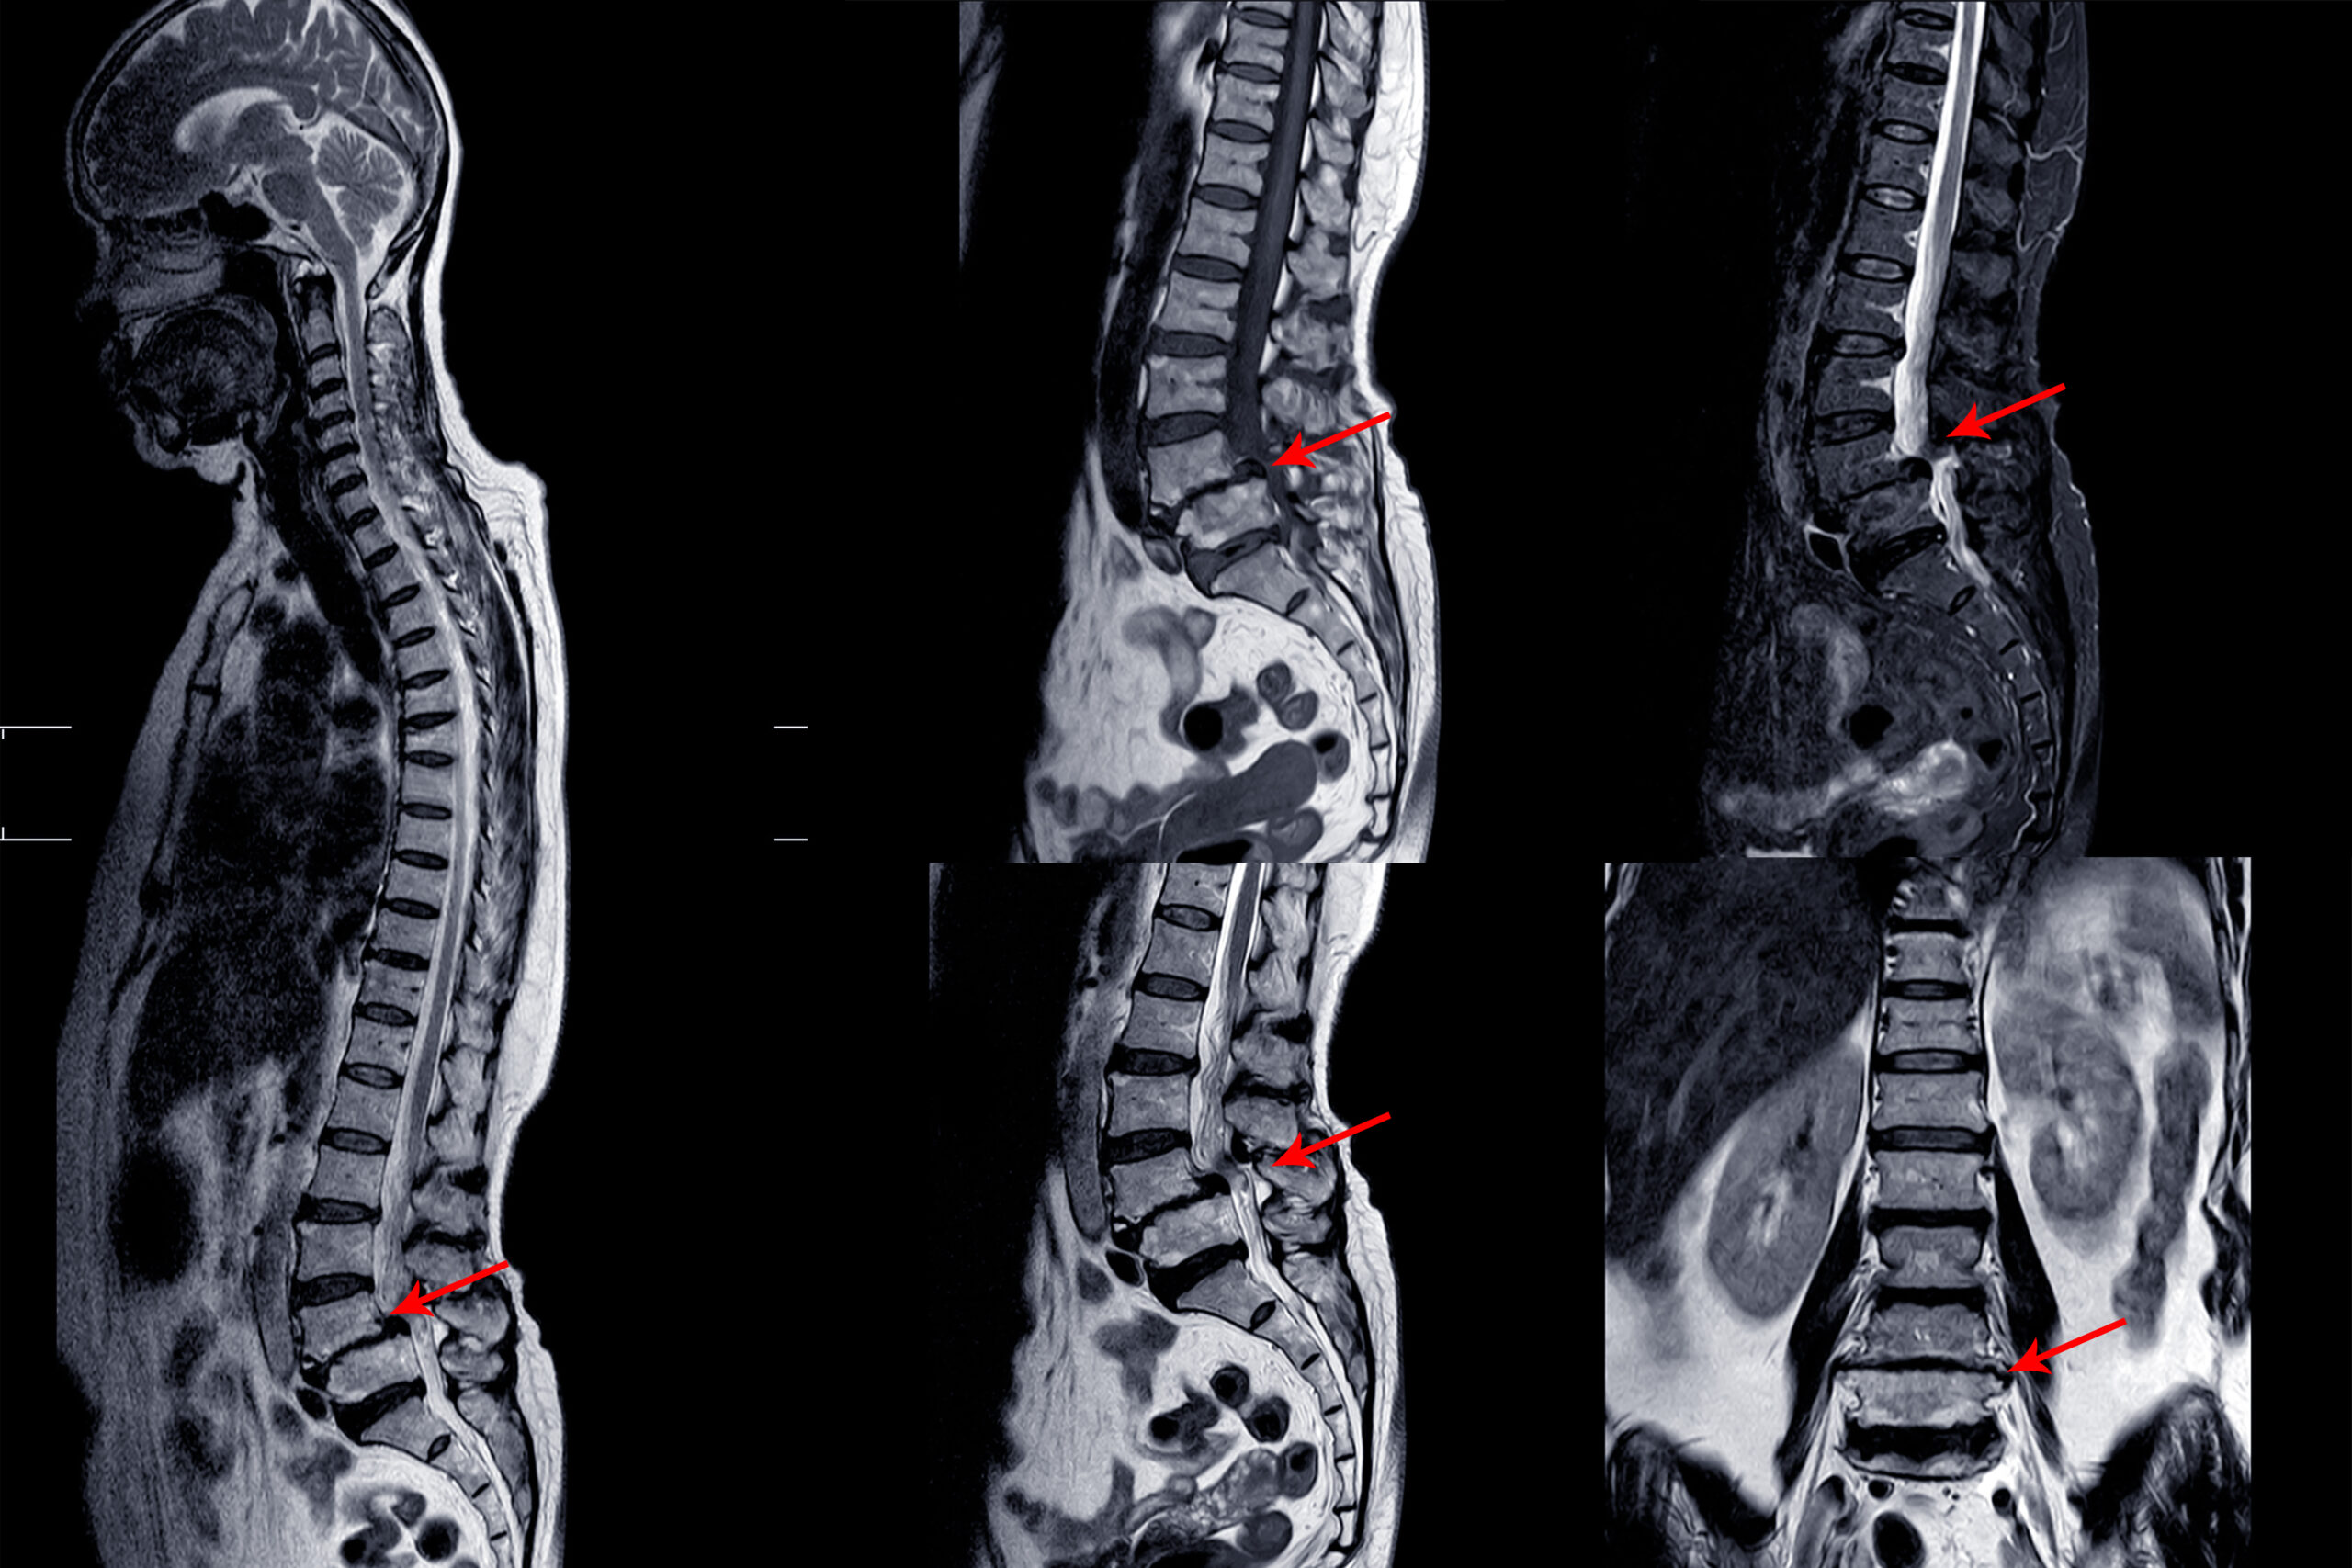

Lower back pain, radiating leg pain, or spinal instability caused by degenerative spine disorders can significantly affect a person’s mobility and lifestyle. As spinal surgeries continue to evolve, less invasive and more effective techniques are emerging. One such advanced method is Oblique Lumbar Interbody Fusion (OLIF) — a cutting-edge procedure that offers excellent spinal stability with reduced tissue damage and faster recovery.

OLIF (Oblique Lumbar Interbody Fusion) is a minimally invasive spinal fusion surgery that targets the lumbar (lower back) region. Unlike traditional posterior approaches that go through the back muscles, OLIF takes an oblique (angled) path through the abdomen’s side, avoiding major muscles and nerves. This approach minimizes trauma to soft tissues, reduces postoperative pain, and speeds up recovery.

Conditions Treated with OLIF

OLIF is typically recommended for patients suffering from:

- Degenerative disc disease

- Lumbar spondylolisthesis (vertebral slippage)

- Disc collapse with nerve root compression

- Spinal stenosis

- Mild to moderate scoliosis

- Recurrent lumbar disc herniation

How is OLIF Performed?